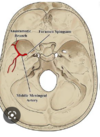

Which arteries do the arrows point to? [1]

Lenticulostiate arteries